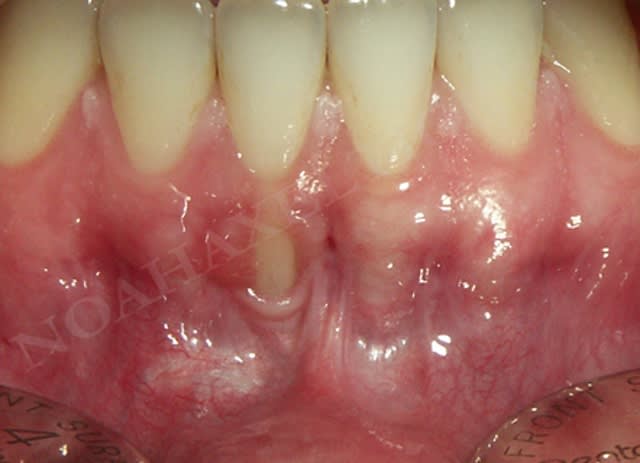

En ce qui concerne la mobilité dentaire, c'est une notion que j'ai appris par le biais du cas suivant :

la patiente présente des rétractions gingivales au niveau du bloc incisivo canin inférieur suite à un traitement parodontal initial. Le problème paro de la patiente est sous contrôle et la patiente désire améliorer l'environnement gingival de 33 à 43.

Très bien madame, on y va :